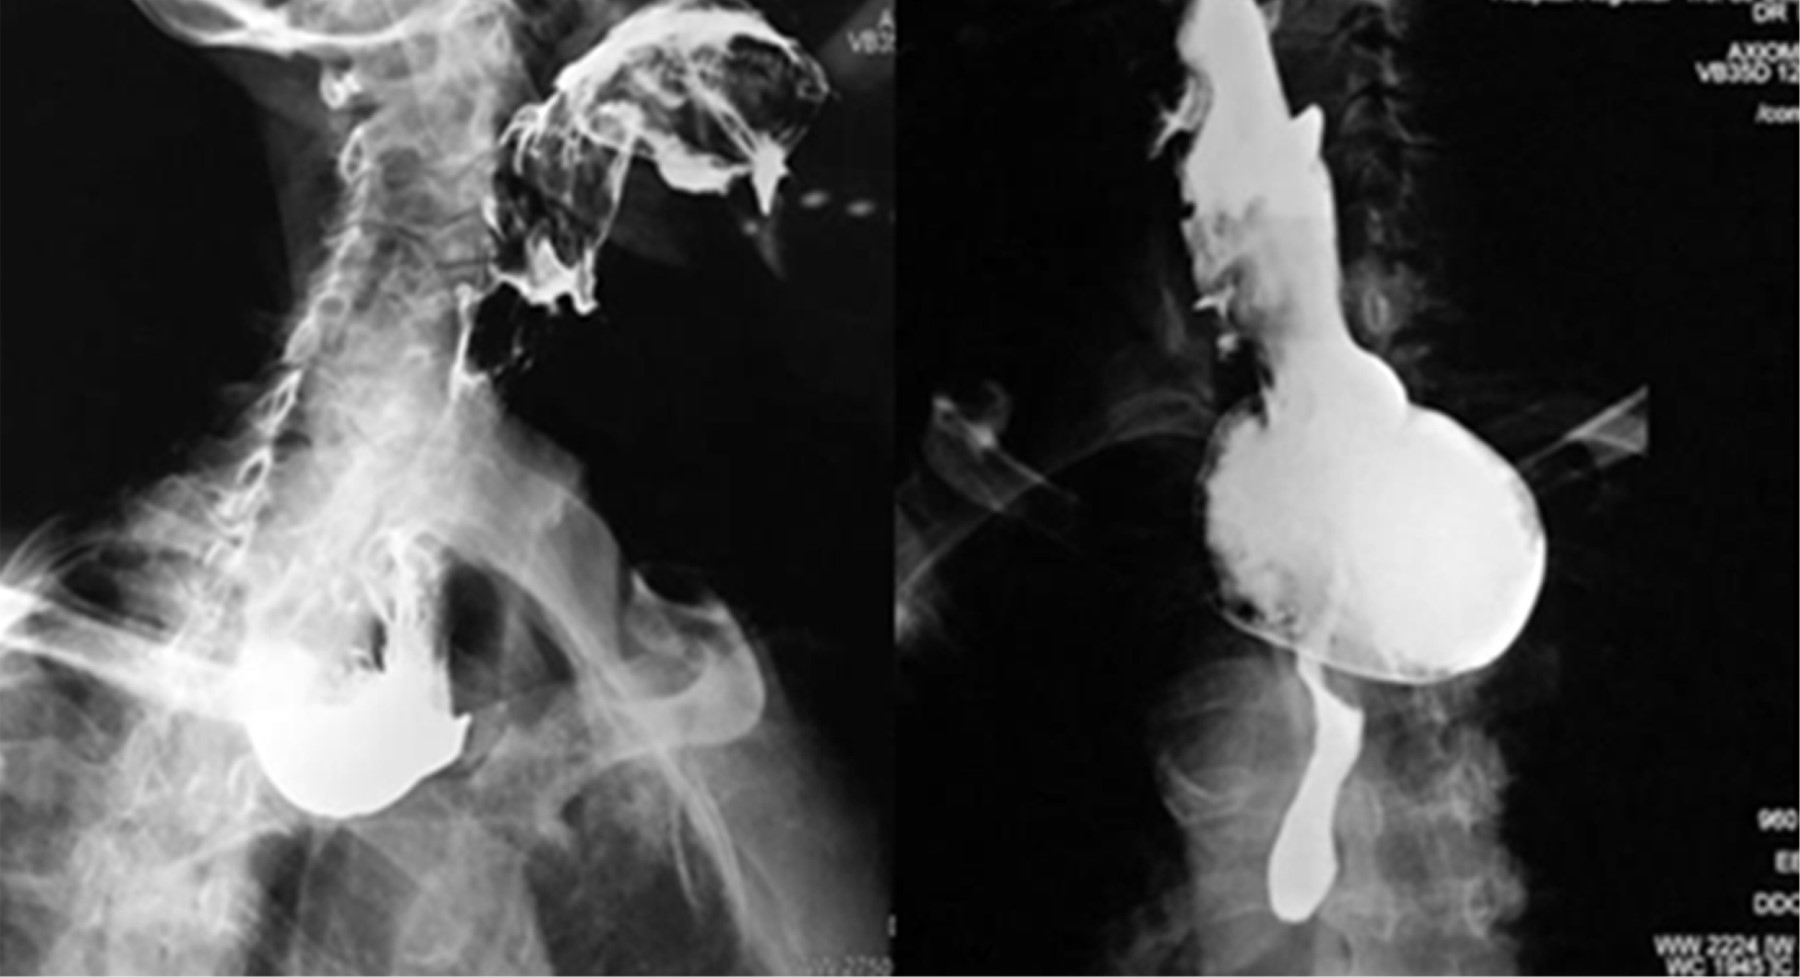

All patients were taken for clinical demographics such as age, sex, time of symptom evolution and predominant symptoms, characteristics of the diverticulum, remission of symptoms and need for re-intervention. The diagnosis of Zenker's diverticulum was made using a radiological contrast study (esophagogram with barium contrast medium) and endoscopy, which confirmed the diagnosis and calculated the size of the diverticulum (Figure 1).

Figure 1